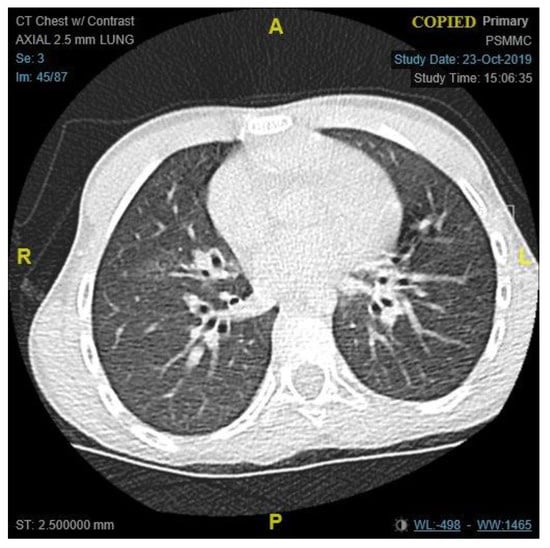

The patient condition necessitated a multidisciplinary approach, involving several sub-specialties, and requiring multiple laboratory workup and diagnostic procedures. Her initial workup, constituting of full blood count, electrolyte, and blood gases, were all within normal limits (Table 1). Similar to the findings of her primary treating hospital, her chest x-ray showed patchy infiltrates, primarily over the lower zones (Figure 2). It was consistent with the results of the computed tomography (CT) scans of the chest, which illustrated the presence of bronchiectasis involving the lower zones (Figure 3). Moreover, she underwent bronchoscopy and bronchoalveolar lavage a few days after starting antibiotics. Bronchoscopy findings showed mild erythematous change of the airway with no purulent secretions distally, while the lavage showed no growth of any bacterial organisms, including acid-fast bacilli. Although endoscopy failed to demonstrate any anatomical abnormality, severe reflux was noted on the barium swallow test (Figure 4). To assess the copious nasal discharge, the patient underwent a CT sinus scan and nasopharyngeal scope, confirming the diagnosis of infectious ethmoid and maxillary sinusitis on a background of allergic rhinitis. Immunological workup was carried out to rule out any primary immunodeficiency conditions, including lymphocyte subsets, immunoglobulin subclasses, tetanus, and diphtheria antibodies. All tests, except the lymphocyte subsets, demonstrated a normal result (Table 1). The standard spirometry showed mild partially reversible obstructive airflow limitation with FVC 75%, FEV1 of 65%, FEV1/FVC 71% and mid-expiratory airflow of 45% with 20% improvement post-challenge with bronchodilator.

Figure 3. A chest CT scan, an axial view of lung window, showing cystic changes strongly consistent with bronchiectasis in lower lobes. (A = Anterior, P = Posterior, R = Right, L = Left).